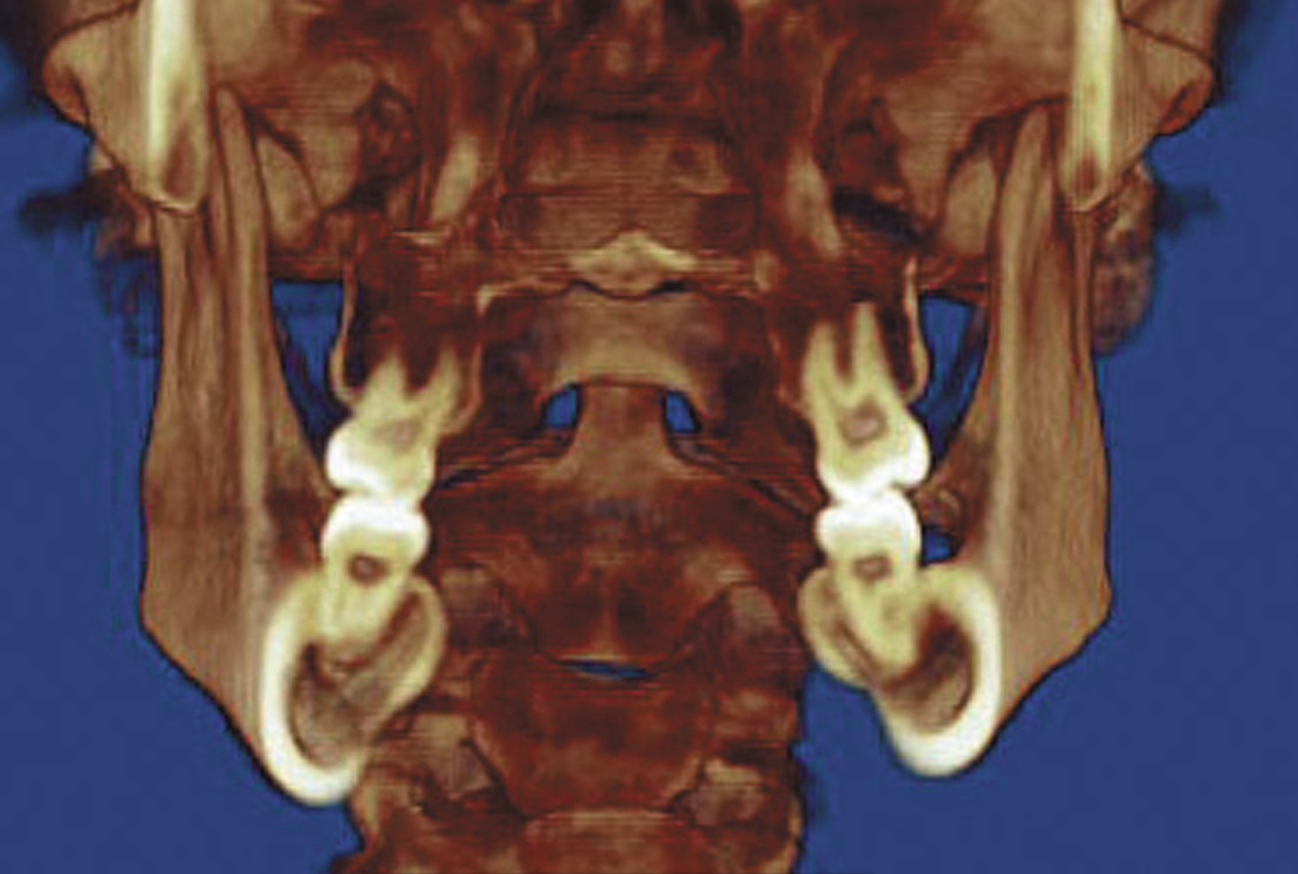

Figure 4A  Coronal section of 3D tomograph revealing axial alignment of posterior teeth. A) Dental alignment does not allow occlusal forces to be directed down long axis of teeth. Maxillary teeth had been tipped to the buccal to compensate for the transverse discrepancy. B) Teeth are positioned to allow occlusal forces to be directed down long axis of teeth.

Figure 4A

Figure 4B  Coronal section of 3D tomograph revealing axial alignment of posterior teeth. A) Dental alignment does not allow occlusal forces to be directed down long axis of teeth. Maxillary teeth had been tipped to the buccal to compensate for the transverse discrepancy. B) Teeth are positioned to allow occlusal forces to be directed down long axis of teeth.

Figure 4B